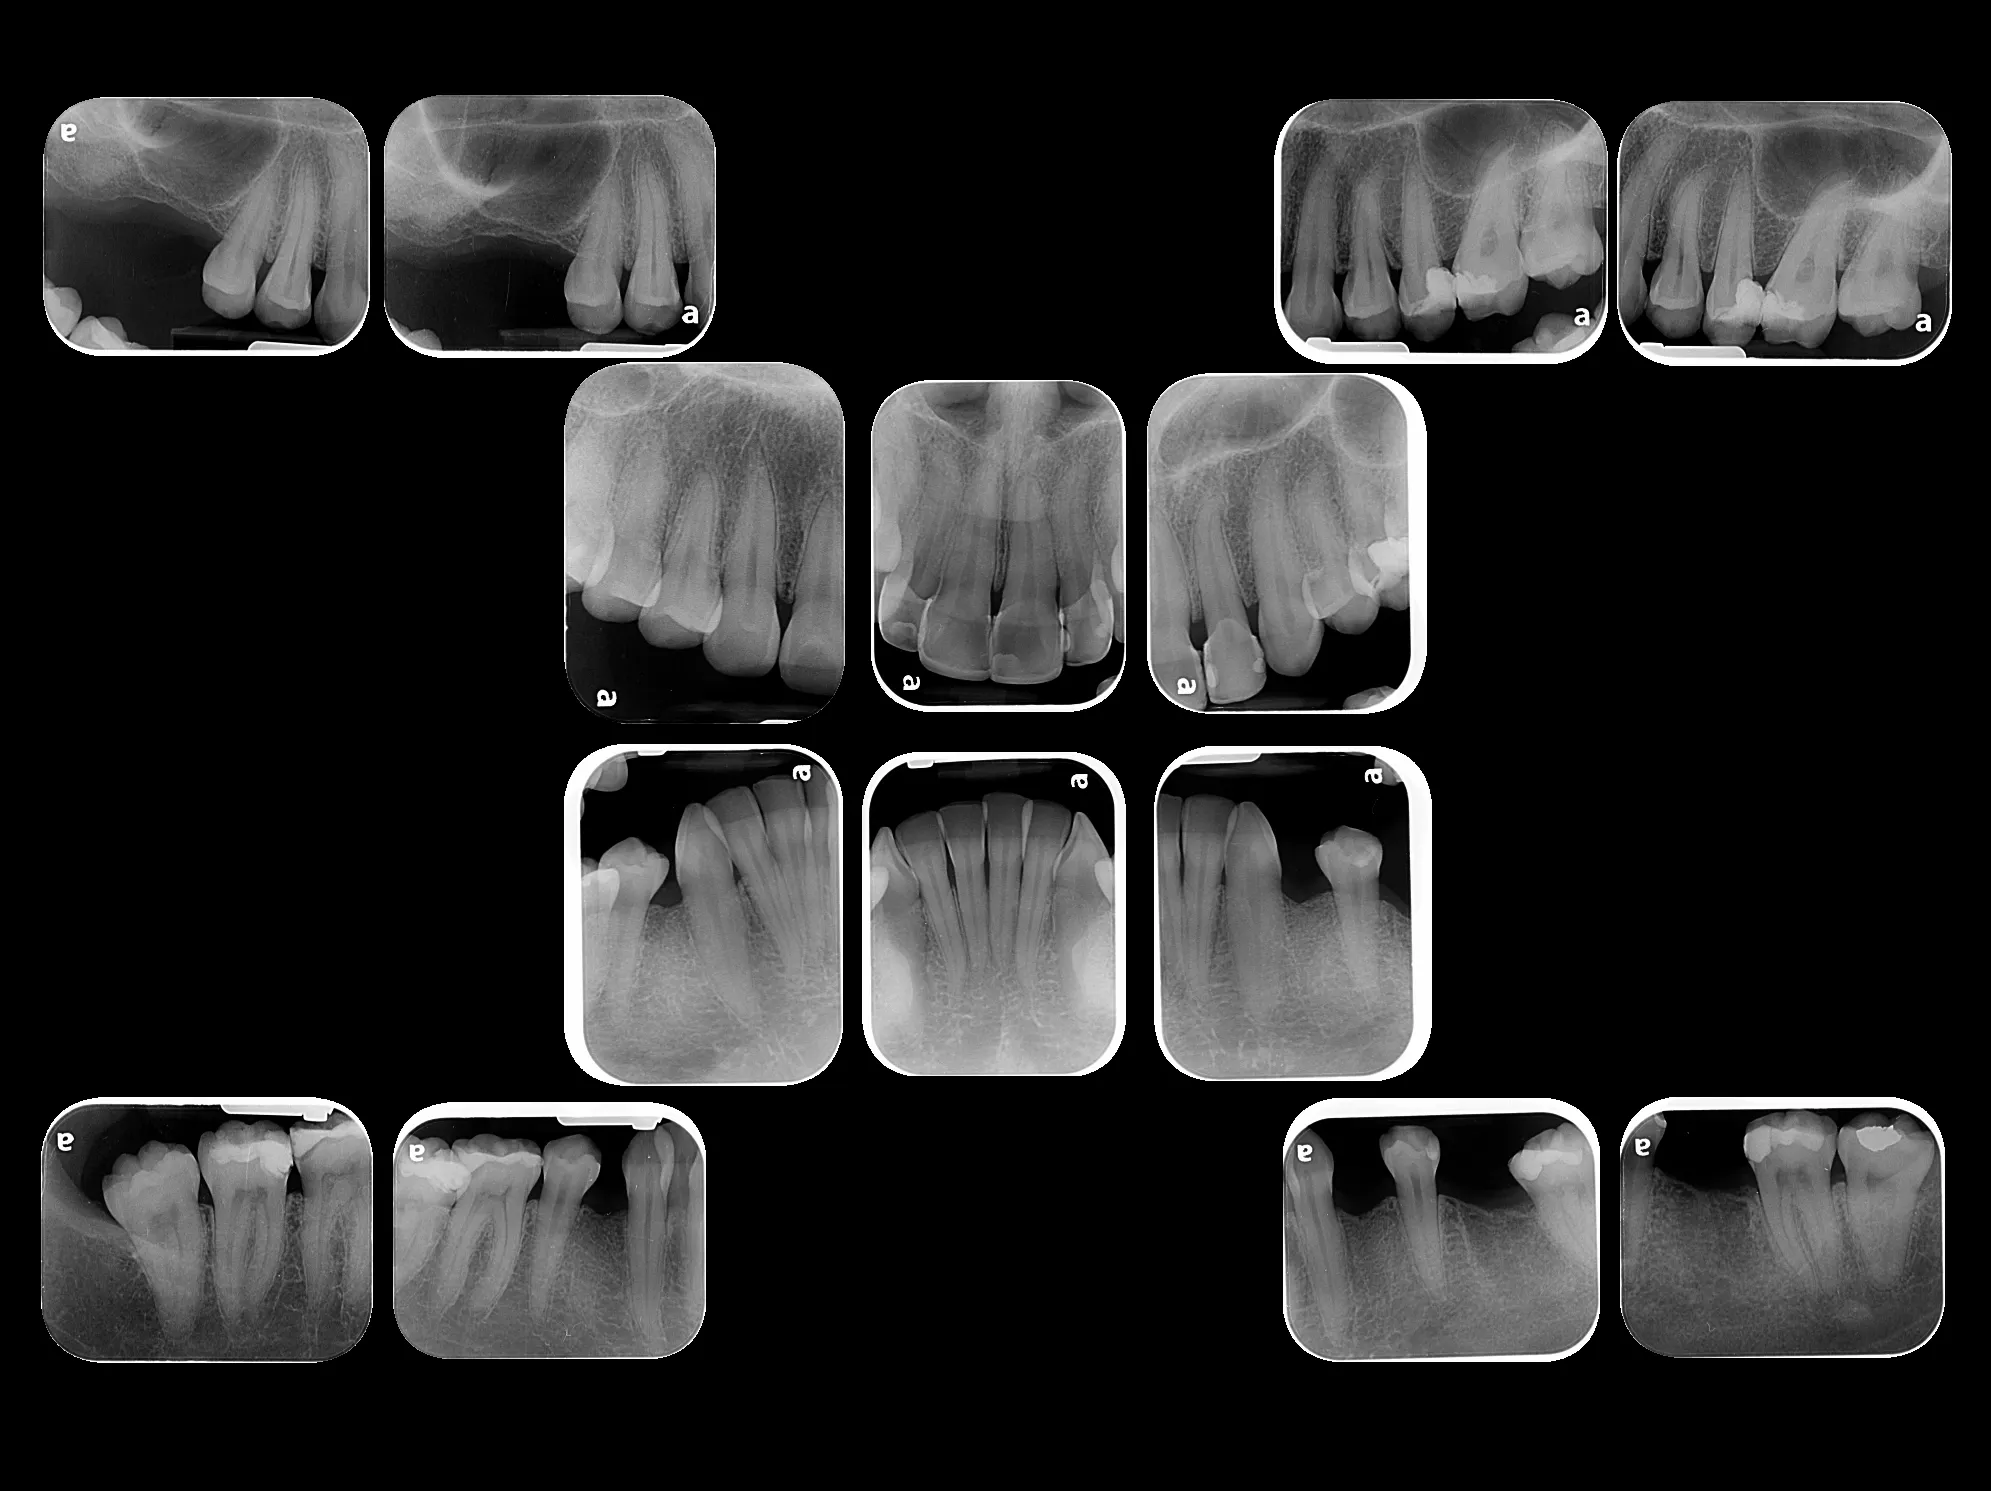

La radiografía intraoral permite observar con gran detalle los dientes y las estructuras que los rodean. Es una herramienta fundamental para detectar caries, infecciones, fracturas, alteraciones en la raíz dental o en el hueso de soporte.

• Procedimiento rápido, cómodo y completamente seguro.

• Resultados inmediatos con excelente calidad de imagen.

• Ideal para tratamientos de endodoncia, implantología y control preventivo.